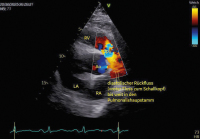

Abbildung 2: Gleicher Patient wie in Abb. 1, apikaler Blick auf die Trikuspidalklappe, die sich kaum bewegt und auch in der Systole offen bleibt, sodass eine schwere TI resultiert. Auch die TK ist im gesamten schwer sklerotisch und unbeweglich. BEMERKUNG: Wenn man gleichzeitig eine unbewegliche TK und PK sieht, sollte man an ein Karzinoid-Syndrom denken!